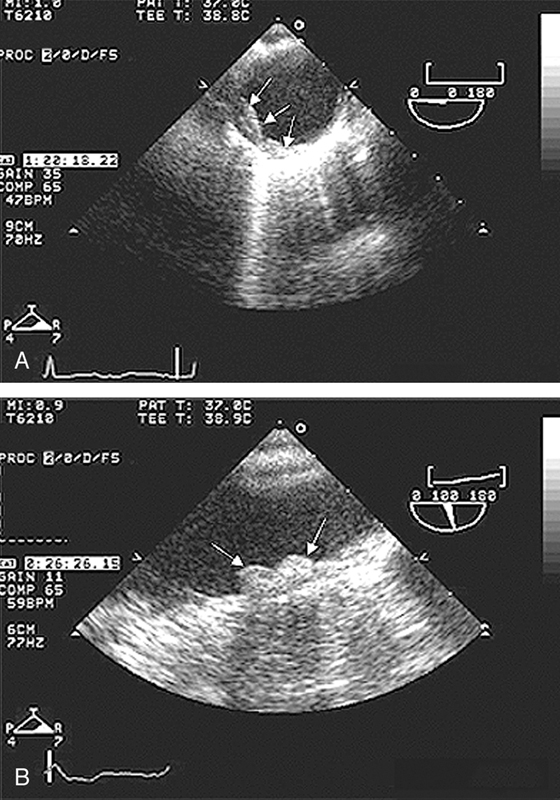

فحوصات تشخيصية لبعض امراض القلب والشرايين التاجية